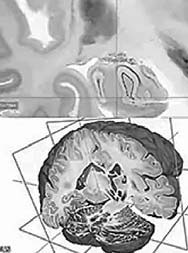

Bilingual: Scientists have created a high-resolution 3-D atlas of the human brain. The digital three-dimensional model called "BigBrain" was made using thousands of sections from the brain of a 65-year-old woman. The resolution is finer than a human hair, so it can reveal clusters of the brain.

Photo